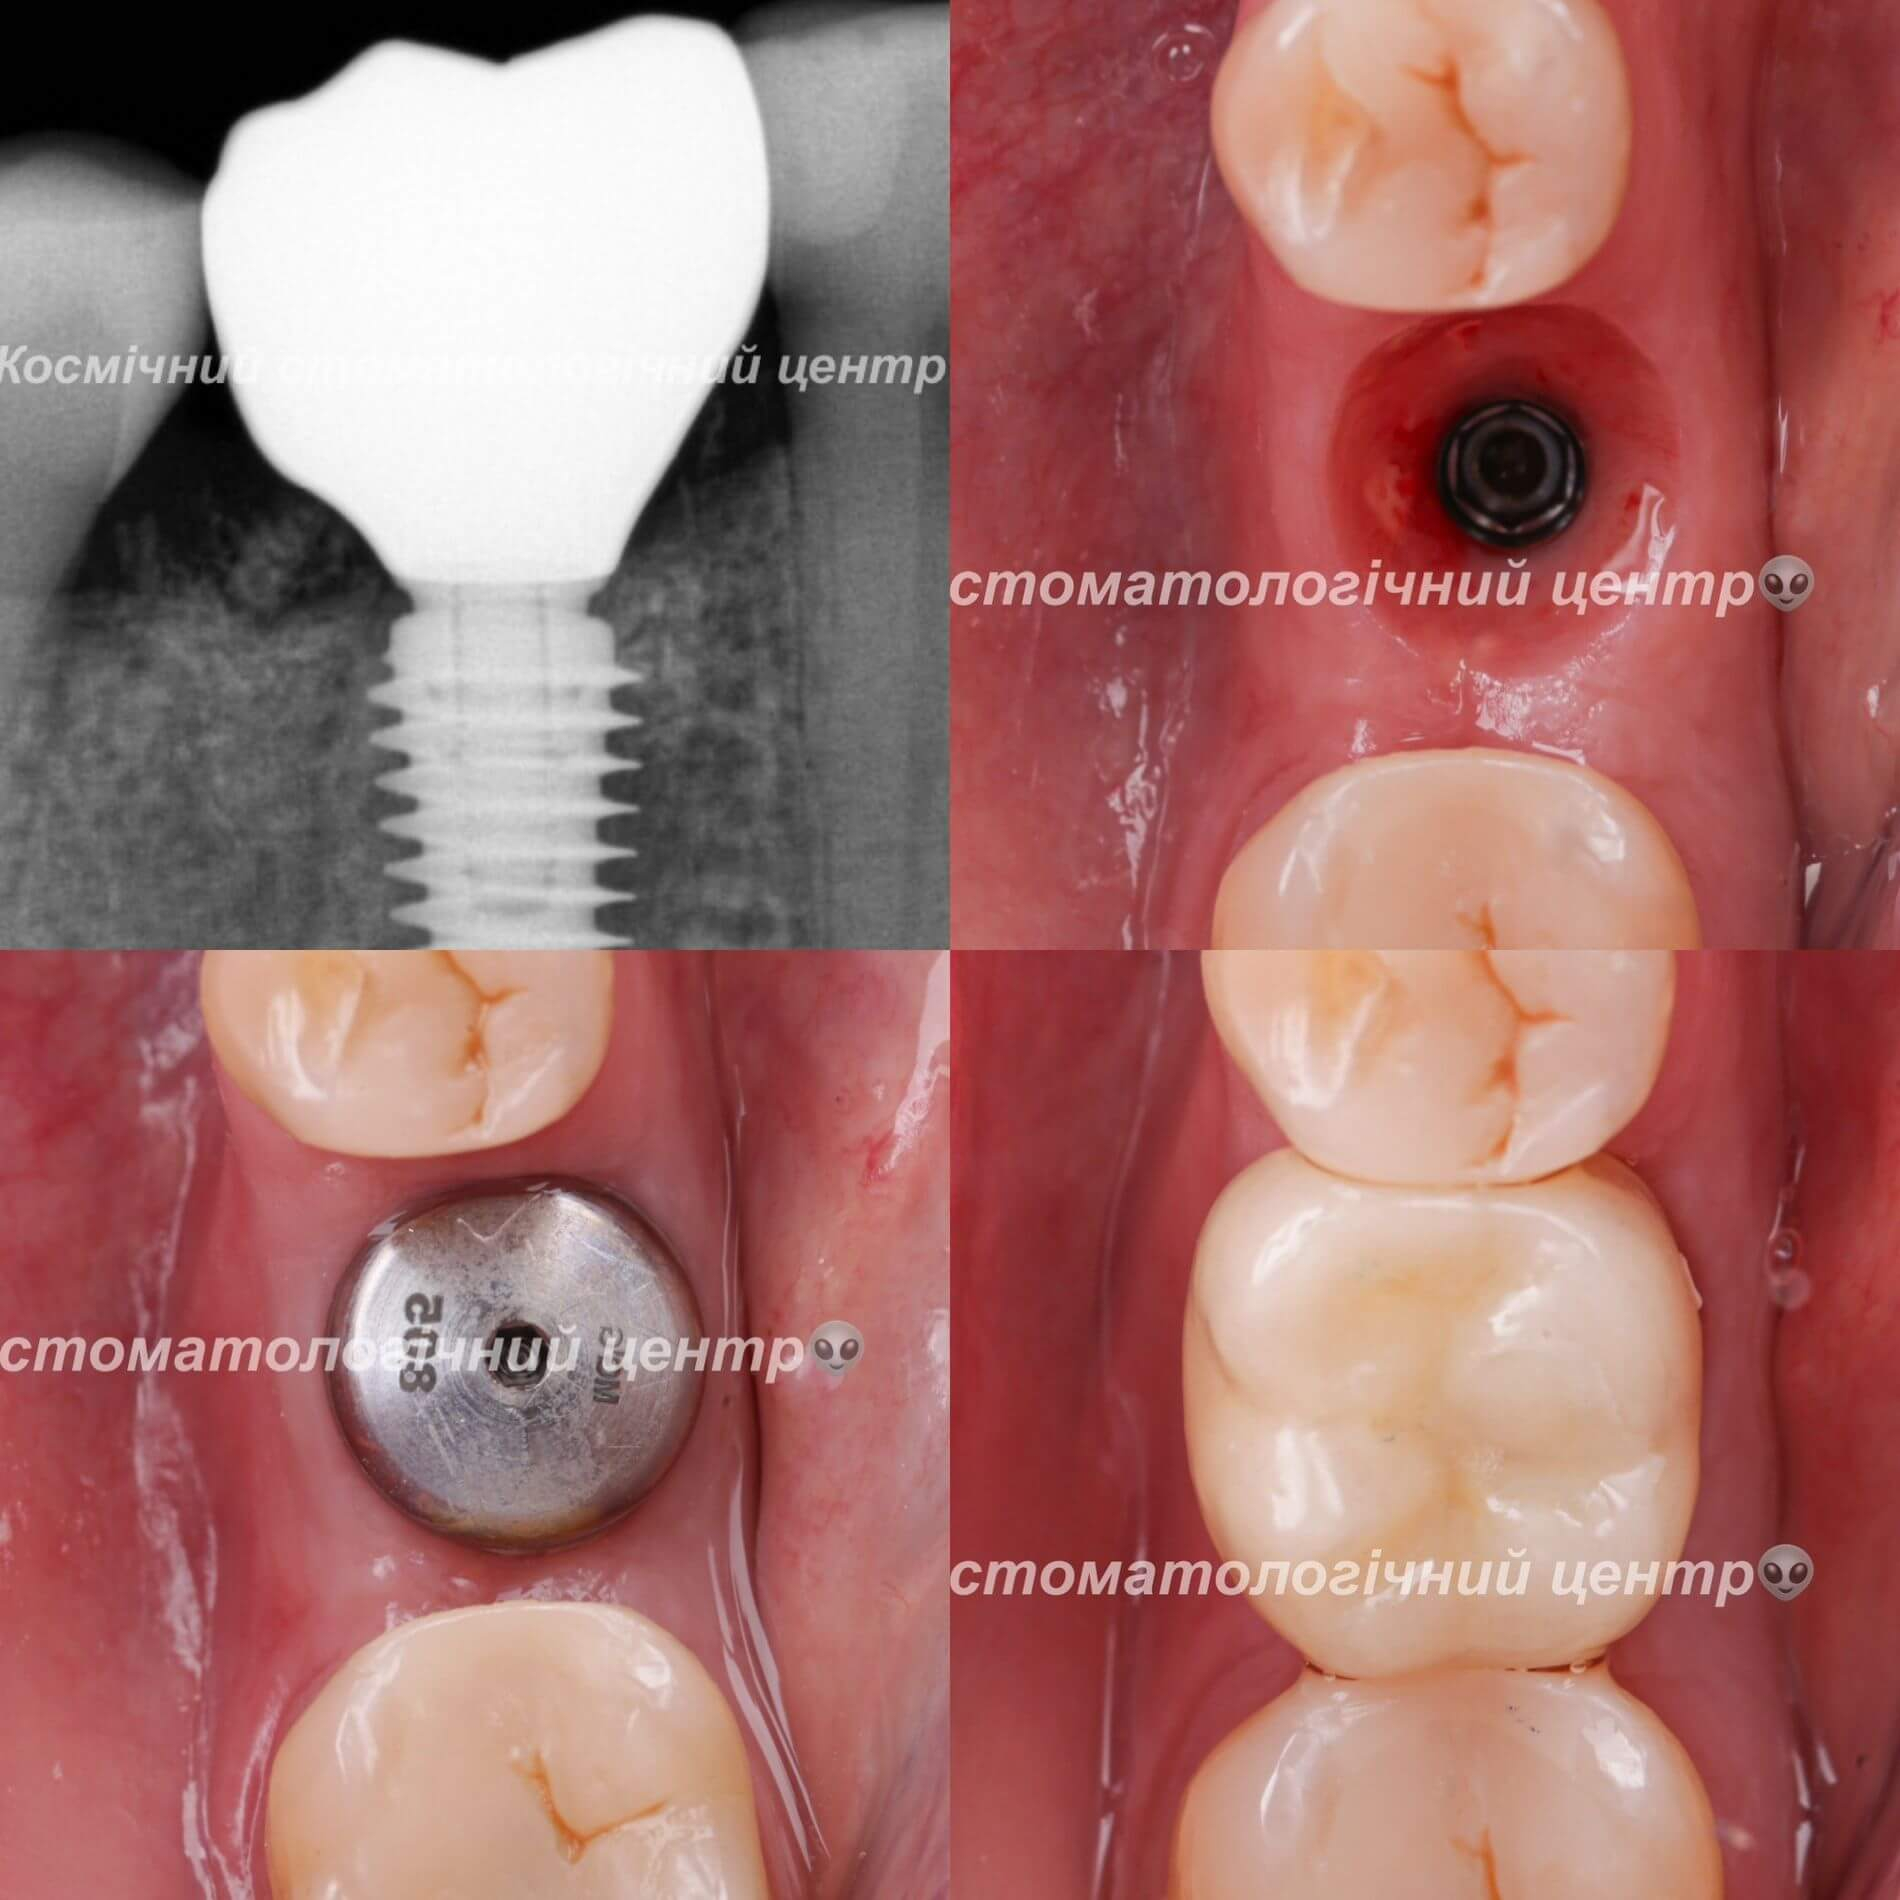

Галерея